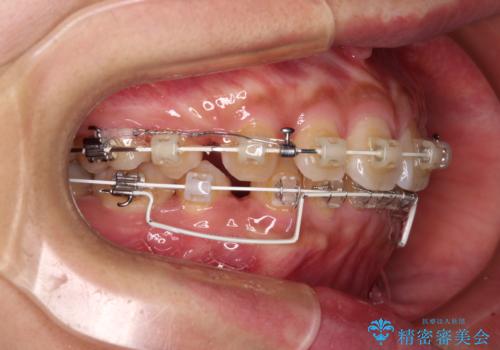

- 矯正装置

- 審美装置

- 前歯の突出感を気にして来院された患者様です。

咬合力が非常に強く、咬合力で前歯が前方に押し広げられており、上下唇に閉じにくさが認められました。

上下左右の第一小臼歯4本を抜歯し、ワイヤー装置にて矯正治療を行うこととしました。

強い咬合力により前歯の隙間がなかなか閉じられず、治療期間は長いものとなりましたが、横顔の印象が大きく変わるほど口元の印象を改善することができました。